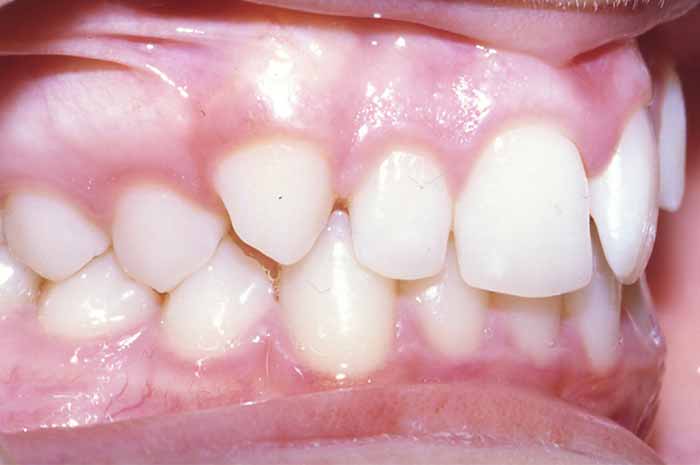

Problema:

Mordida cruzada anterior

Uno o varios incisivos superiores se situan por detrás de los inferiores, pudiendo alterar el correcto cierre de la boca.

Tratamiento realizado:

Ortodoncia convencional con brackets metálicos

En este caso, para conseguir un resultado óptimo, también se utilizó un aparato removible (de quita y pon) en la arcada superior, previo a la colocación del aparato fijo (brackets).

La excepcional colaboración de la paciente fue fundamental para la consecución de los resultados.

Antes y Después